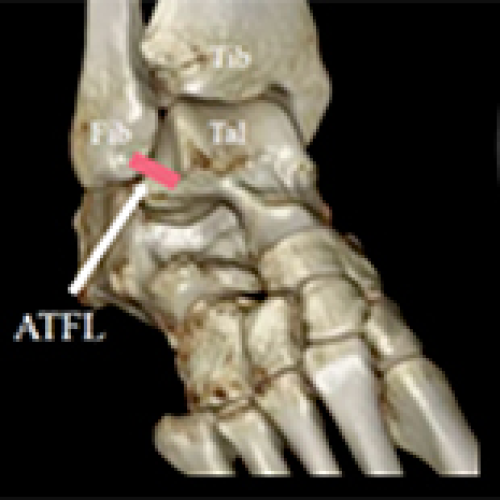

Anterior Talofibular Ligament All-Inside Arthroscopic Reconstruction with InternalBrace™ for Chronic Lateral Ankle Instability

Guang-Long Zeng, Li-Min Cai

DOI: 10.12659/MSM.937699

Med Sci Monit 2022; 28:e937699

06 Oct 2022 : Clinical Research

Guang-Long Zeng, Li-Min Cai, QingXiang Xie, Hao-Bo Huang, Yong-Cong Li, Bo-Yuan Su

6,244